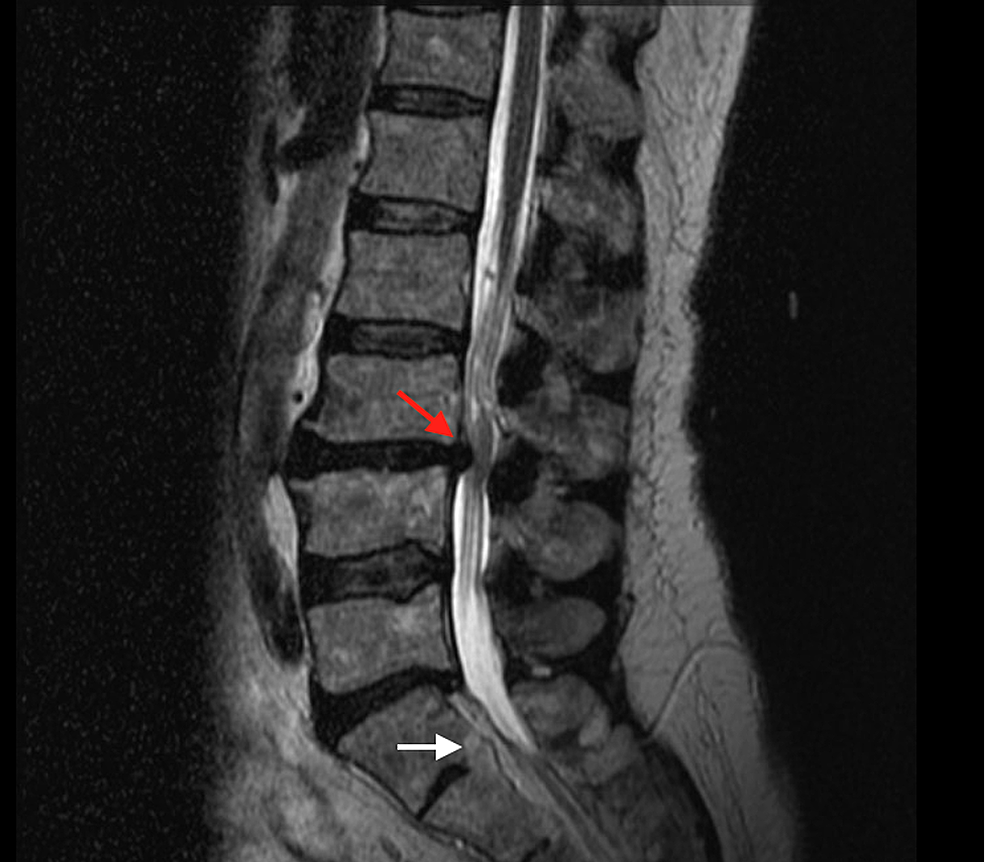

From www.researchgate.net

Preoperative MRI of the lumbar spine. A T1weighted image What Is Autofusion Of The Spine Fusion can be congenital or acquired as. for a patient with advanced ankylosing spondylitis, autofusion of the spine’s motion segments can lead to long levers of fused spinal segments that. a multilevel spinal fusion surgery involves fusing 2 or more motion segments of the spine to become one single unit. This surgery is designed to improve. a. What Is Autofusion Of The Spine.